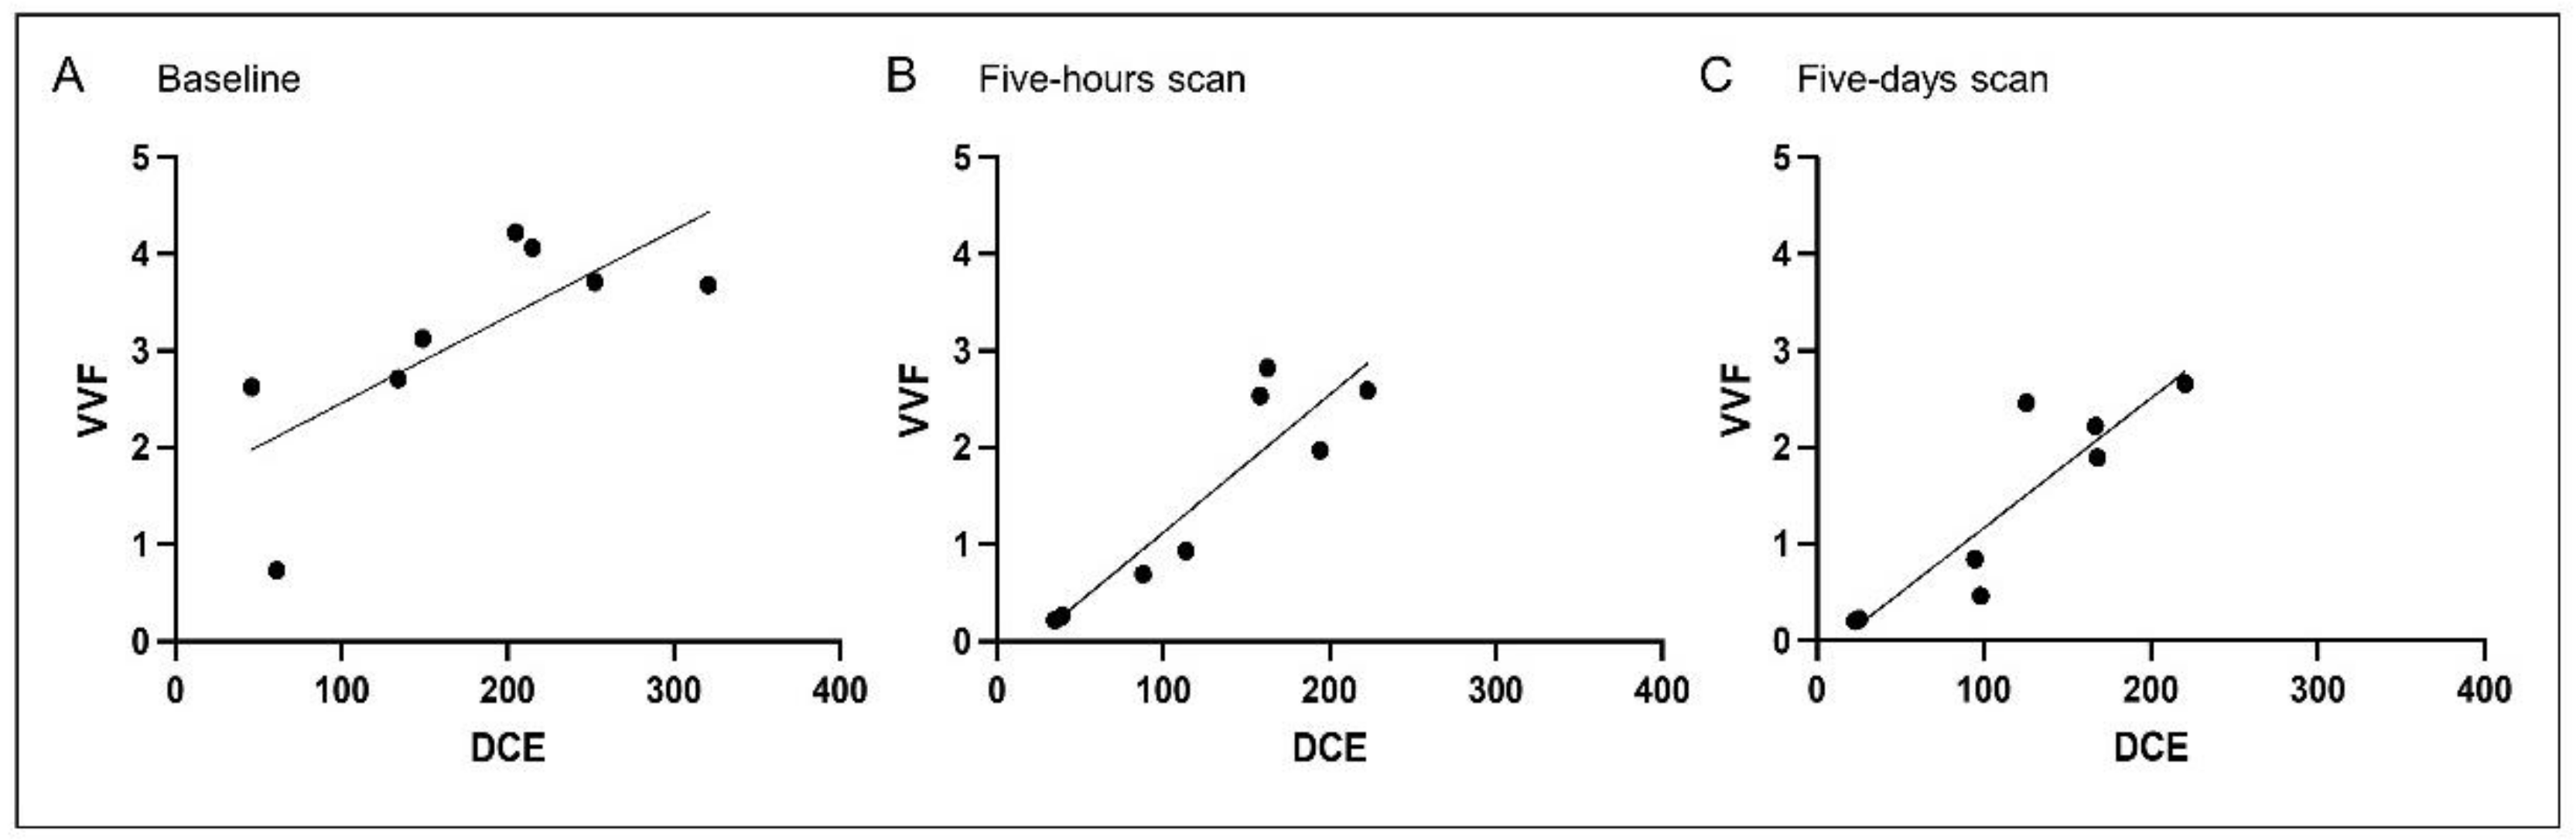

3.2. Correlation Analysis